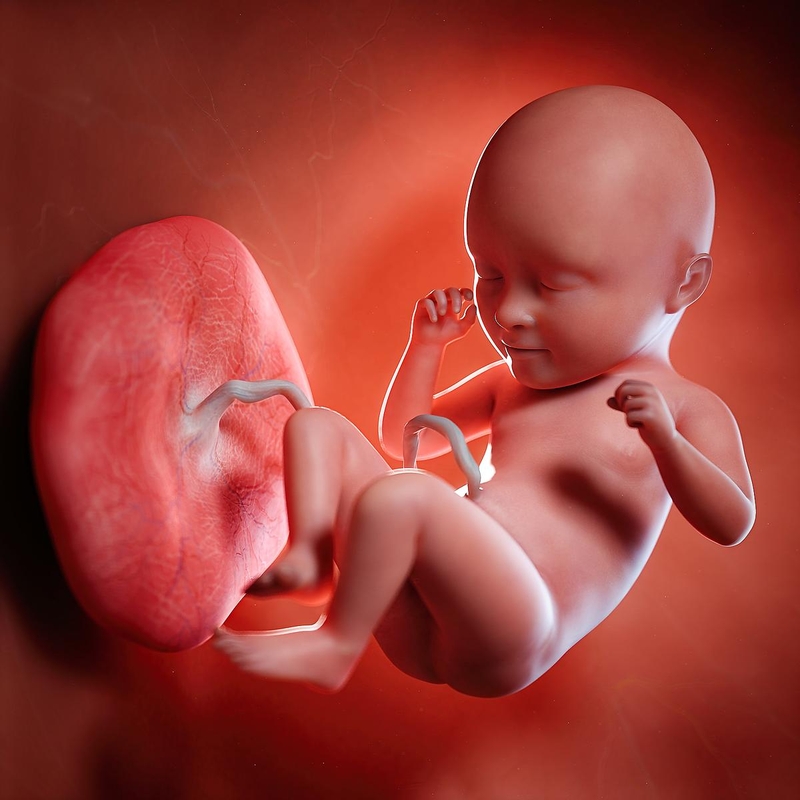

xét nghiệm dị tật thai nhi ở tuần thứ mấy tốt nhất Cơ thể trẻ trong khoảng thời gian từ 12 - 14 tuần đã phát triển một số bộ phận